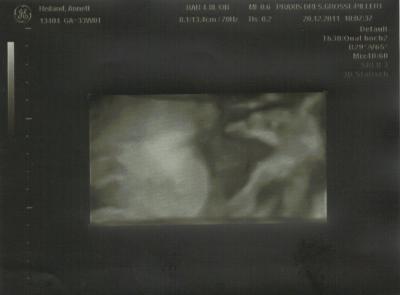

hatte heute wieder FA termin und bin heute auch in die 34. ssw gekugelt. hab gleich meine bescheinigung für den mutterschutz bekommen, muss ich jetzt nur noch ausfüllen und abschicken. also beim CTG wollte mausi nicht so wirklich mit machen, hat ständig dagegen getreten, aber nach ner weile hats dann doch funktioniert. Dann wurde gleich noch ein Abstrich gemacht und nach dem mumu geschaut. also mumu ist zu und gebärmutterhals ist bei 4,5 cm, also alles in ordnung. mausi ist jetzt 2.267 gr. schwer, ist laut ärztin ihrer tabelle 44 cm groß. aber oberschenkelknochen war bei 6,7 cm und wenn ich das mal 7 rechne, komme ich auf 46,9 cm. mmh, na ja. dann hab ich endlich, nach 10 langen wochen mal wieder ein bildchen bekommen. ist zwar ziemlich groß aufgenommen, aber man kann das köpfchen im seitenprofil sehen, man kann nase, auge, mund und ein ohr sehen. ist zwar etwas verschwommen, aber zu erkennen. ach noch was. war ich doch vor 3 wochen froh, das sie sich endlich in SL gedreht hat, so hab ich heute erfahren, das sie wieder in BEL liegt. na ja, warum auch nicht. kenne das von meinen beiden jungs nicht, die lagen von anfang an in SL und haben sich nicht einmal gedreht. na ja, weiber halt, machen was sie wollen (so die aussage von meinem mann) so, anbei noch das bildchen von meiner maus. in 2 wochen hab ich dann den nächsten termin, bin dann 36. woche und hoffe mal das sie sich wieder gedreht hat. lg annett

Bild zu so wieder da vom FA - Forum für Februar - Mamis